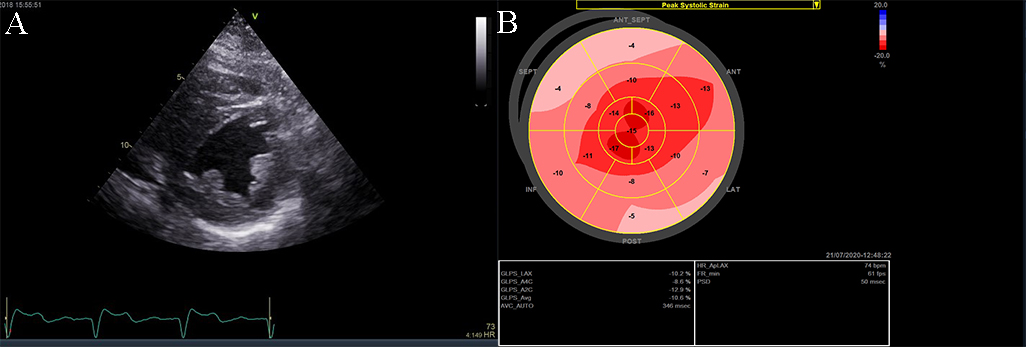

Fig. 9.The echocardiographic aspect of cardiac amyloidosis, associated with aortic stenosis. (A) short-axis view, showing left ventricular hypertrophy. (B) Speckle tracking echocardiography obtained by measuring longitudinal strain in apical 4 chamber view, shows a significantly reduced GLS (global longitudinal strain) of –8.6%.

The causes of RCM can be classified as non-infiltrative (familial) or infiltrative (storage diseases), but the same pattern can be found in other disorders like diabetic cardiomyopathy, scleroderma, and endomyocardial fibrosis [38, 39, 40]. An accurate myocardial investigation by MRI and myocardial scintigraphy allows the diagnosis of different types of myocardial amyloidosis which is increasingly observed in the elderly either by transthyretin (aTTR) or by AL–light immunoglobulin chains in different plasmacytomas [41]. Another type of RCM is found in sarcoidosis and it can cause global or regional LV wall motion abnormalities. In some cases, the changes are specifically revealed on the basal posterior and lateral wall of the LV [42, 43, 44]. The most common finding is myocardial thinning, but RCM can also present with hypertrophy or it can include myocardial aneurysms [38, 45, 46, 47]. In some RCMs such as endomyocardial fibrosis or hypereosinophilic syndrome apical intraventricular thrombosis may be recognized; this may be responsible for pulmonary or systemic cardioembolism [48]. In RCM due to amyloidosis, apart from hypertrophy and wall motion abnormalities (Fig. 9), valvular involvement may also be noted with thickened aortic cusps or mitral leaflets determined by local deposition of amyloid [49].

2D echocardiography, as mentioned before, highlights a low or normal diastolic volume of the LV associated with normal or only mildly reduced LV ejection fraction, as criteria for RCM. Also, one or both atrial enlargement is identified, with increased pressures, and normal pericardium. Once the typical pattern of RCM is identified, the echocardiogram can reveal also some features for a specific etiology. For example, in cardiac amyloidosis, the left and right ventricular walls are often mildly and symmetrically thickened, the myocardium may have a granular appearance, and myocardial strain imaging may show preserved apical function. However, it is not sufficient information neither to confirm, nor exclude cardiac amyloidosis [39, 40, 50], and further testing is needed. Moreover, in sarcoidosis global or regional (typically basal posterior and lateral) LV wall motion abnormalities may be observed. The most common finding is myocardial thinning, while less common findings include myocardial aneurysms, hypertrophy, and pericardial effusion [51, 52]. In eosinophilic inflammation of the myocardium or hypereosinophilic syndrome, the echocardiogram is often unrevealing during the initial necrotic stage. In the thrombotic stage of the disease, the damaged endocardium may have associated thrombus, predominantly involving the ventricular apex [3, 5, 38, 52, 53]. During the last, fibrotic stage, increased endomyocardial echogenicity is seen, affecting one or both ventricles, sometimes with overlying thrombus; the ventricular filling can be restricted, and atrioventricular valve leaflets may be tethered [53, 54, 55]. A pattern similar to hypereosinophilic syndrome can emerge in endomyocardial fibrosis. It may be characterized by LV, RV, or biventricular apical fibrosis [53, 54, 55]. In radiation-induced RCM the echocardiogram may show structural abnormalities within the field of radiation, such as calcified heart valves, a thickened pericardium, or focal wall motion abnormalities related or not to radiation-associated coronary artery disease [40, 42, 56, 57].

Strain echocardiography reveals low myocardial velocities with regional function inhomogeneity. In RCM due to cardiac amyloidosis, both LV and right ventricle (RV) walls are often moderately, or even severely, and symmetrically thickened and the myocardium may have a granular aspect. This aspect cannot be explained by secondary causes such as hypertension. In this case, strain echocardiography may show preserved apical function [45, 46, 47]. Regarding the LA function, strain echocardiography may help in the differential diagnosis between RCM and constrictive pericarditis (CP). In both RCM and CP, the reservoir function of the left atrium is normal or may be increased compared to normal due to higher filling pressure. Contrary to this, both active and passive functions are decreased in RCM. This can be evidenced using global and regional strain, which highlights a lower value compared to normal of the septal LA strain rate [61].